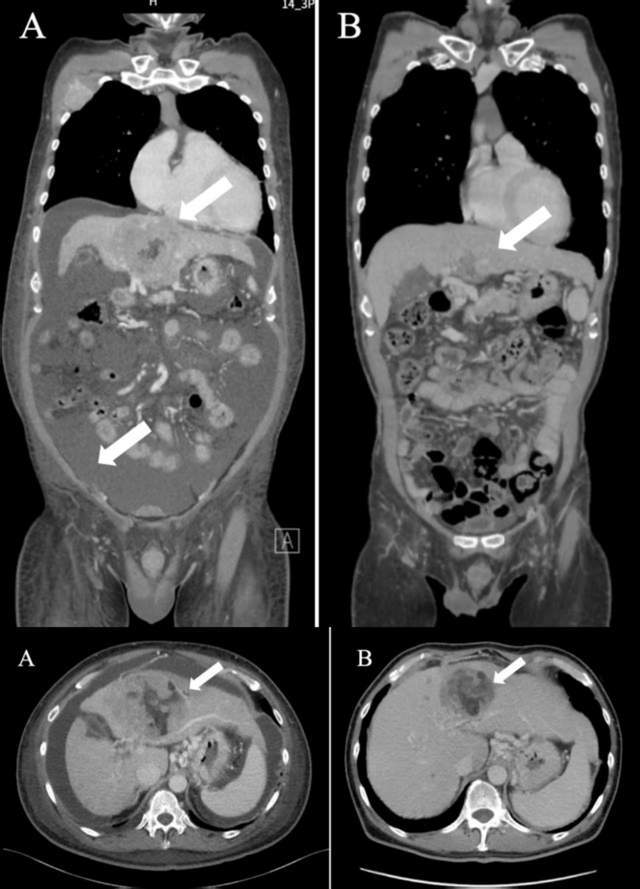

这位61岁晚期肝细胞癌男性患者,伴有多发淋巴结转移、多肺转移和骨转移。采用靶向WT1及α-半乳糖神经酰胺的DC疫苗,联合NK细胞及纳武利尤单抗的三联方案后,患者肿瘤缩小,腹水消失。